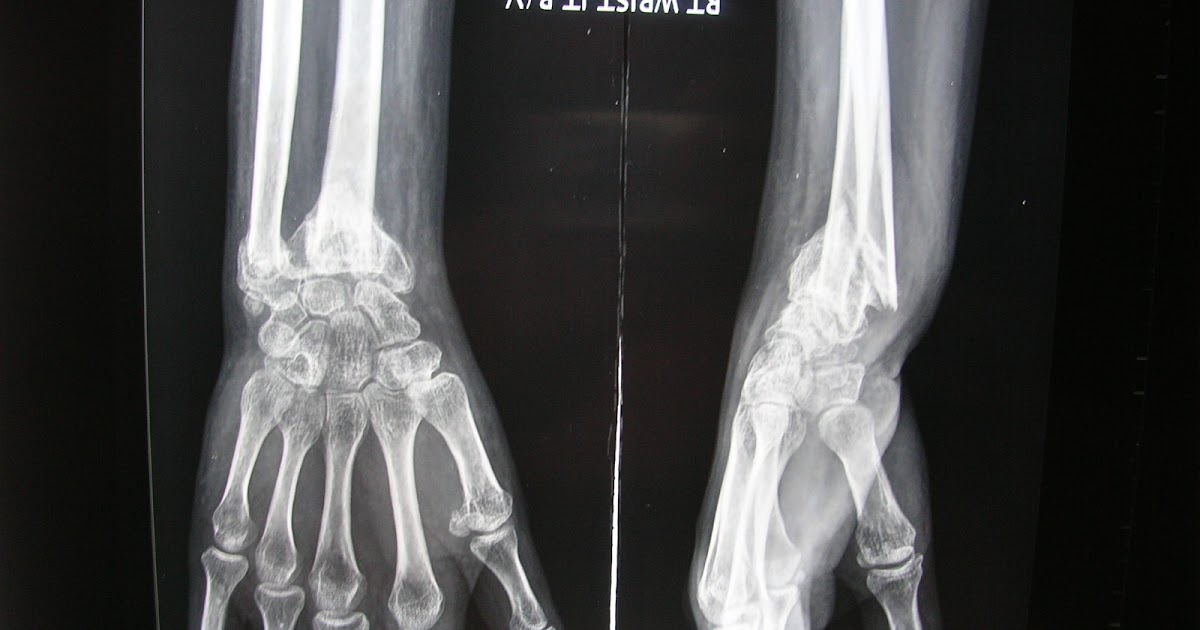

Xrays and Slides malunion of distal radiusulna fracture with Hard Lump On Ulna Bone A moveable wrist bump is typically a ganglion cyst. However, in rare cases, a bump on your fingers, hand, or wrist could be a giant cell tumor, enchondroma, or soft tissue sarcoma. Bone tumors form when bone cells divide and grow out of control, forming a lump or a mass of cells. Other less common causes include fatty tissue growth. Hard Lump On Ulna Bone.